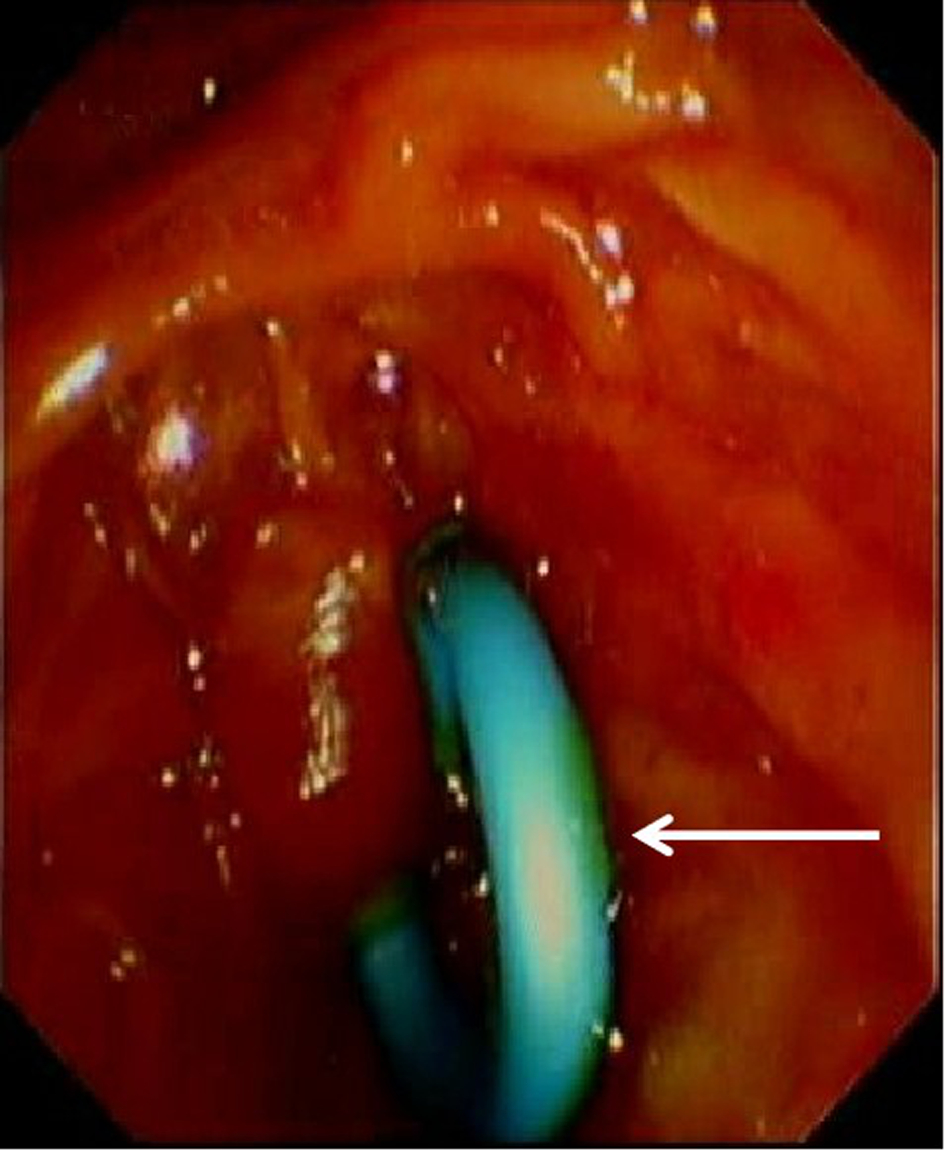

论著_胆道疾病

改良胰管支架用于内镜逆行胰胆管造影取净胆总管结石后胆道引流的安全性及有效性分析

李佳林, 任笠坤, 冉勋, 夏绍萱, 周昱彤, 黄鑫, 韩民

2023, 39(8): 1911-1918. DOI: 10.3969/j.issn.1001-5256.2023.08.021

摘要(1490) HTML (623) PDF (2008KB)(64)

摘要:

目的  探讨改良7Fr胰管塑料支架用于胆道内引流的临床应用价值。  方法  收集2021年4月—2022年6月在贵州医科大学附属医院肝胆外科行内镜逆行胰胆管造影(ERCP)取石后行胆道引流的121例胆总管结石患者的临床资料,根据术后胆道引流方式分为改良支架组(n=59)和鼻胆引流组(n=60),其中改良支架组采用改良7Fr胰管塑料支架引流,鼻胆引流组采用鼻胆管引流,回顾性分析两组患者临床资料,观察改良支架组中支架自行脱落情况,比较两组临床疗效、患者术后舒适度及术后并发症发生率。符合正态分布的计量资料两组间比较采用成组t检验;非正态分布的计量资料两组间比较采用Mann-Whitney U检验;计数资料两组间比较采用χ2检验。  结果  两组结石清除率为100%。两组患者术后住院天数、总住院天数比较,差异均有统计学意义(t值分别为-3.997、2.317,P值均 < 0.05)。两组患者术后血清TBil、DBil、ALP、AST及GGT均较术前明显下降(P值均 < 0.05)。两组患者TBil、DBil、ALP、ALT、AST、GGT术前及术后比较,差异均无统计学意义(P值均>0.05)。改良支架组与鼻胆引流组术后-术前生化指标差值比较,差异均无统计学意义(P值均>0.05)。两组术后24 h内舒适度评分、术后首次进食、进饮时间比较,差异均有统计学意义(t值分别为2.001、3.579、4.604,P值均 < 0.05)。两组并发症比较,差异均无统计学意义(P值均>0.05)。改良支架组支架自行脱落率为83.05%,未发生支架阻塞、移位、断裂、穿孔及感染并发症。  结论  ERCP取净胆总管结石后,应用改良7Fr胰管塑料支架行胆道内引流与鼻胆管引流效果相当,可缩短患者术后住院时长、提升患者术后舒适度,加速患者康复,且支架自行脱落率高,临床应用安全、有效。